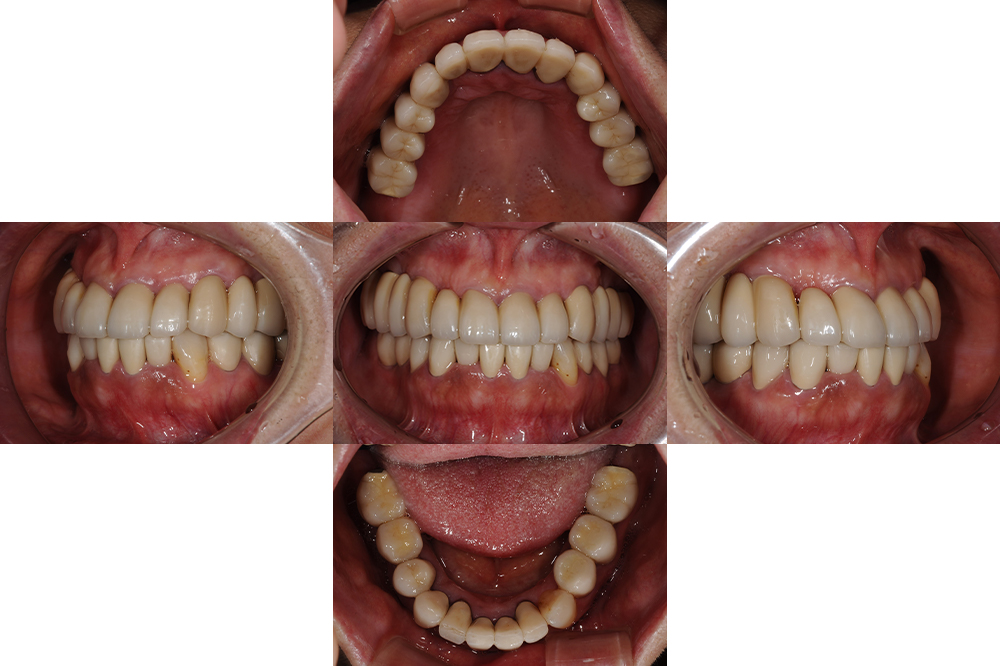

前歯が外れた(50代)インプラント・セラミック修復

年齢 53歳

性別 女性

主訴 前歯が外れた

治療内容 ・インプラント

・セラミック修復

治療期間 1年半

治療費用 430万円

治療経過 上顎は前歯以外は保存不可能と診断した

上顎の前歯も状態が万全ではないため、上顎総義歯も治療計画の1つであったが、固定式の歯を希望されたため上顎は前歯以外をインプラントにて、下顎は予後不良な奥歯を抜歯しインプラントにて咬合再構成をおこなった

現在術後5年が経過しているが不安のあった上顎前歯も問題なく機能している。

インプラントを使用することで残存歯の温存につながった症例である。

After